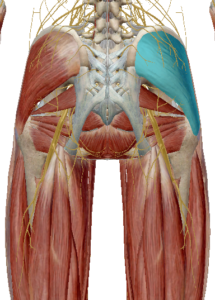

(3) 중둔근과 소둔근

중둔근은 고관절 측면 안정성에 중요한 근육입니다.

수축 시 고관절 외전과 섬유의 위치에 따라 내회전과 외회전도 관여한다고 합니다.

소둔근도 중둔근과 같이 고관절 측면 안정성에

중요한 역할을 합니다.

고관절 외전을 발생시키며 고관절 앞쪽에 연결되어 있어 고관절 굴곡과 내회전을 발생합니다.